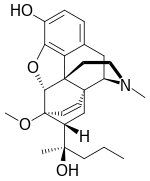

| Oripavine derivatives | ||||

|---|---|---|---|---|

7-PET 7-PET |

Acetorphine Acetorphine |

Alletorphine Alletorphine |

BU-48 BU-48 |

Buprenorphine Buprenorphine |

Cyprenorphine Cyprenorphine |

Dihydroetorphine Dihydroetorphine |

Etorphine Etorphine |

Homprenorphine Homprenorphine |

18,19-Dehydrobuprenorphine 18,19-Dehydrobuprenorphine |

N-cyclopropylmethylnoretorphine N-cyclopropylmethylnoretorphine |

Nepenthone Nepenthone |

Norbuprenorphine Norbuprenorphine |

Thevinone Thevinone |

Thienorphine Thienorphine |